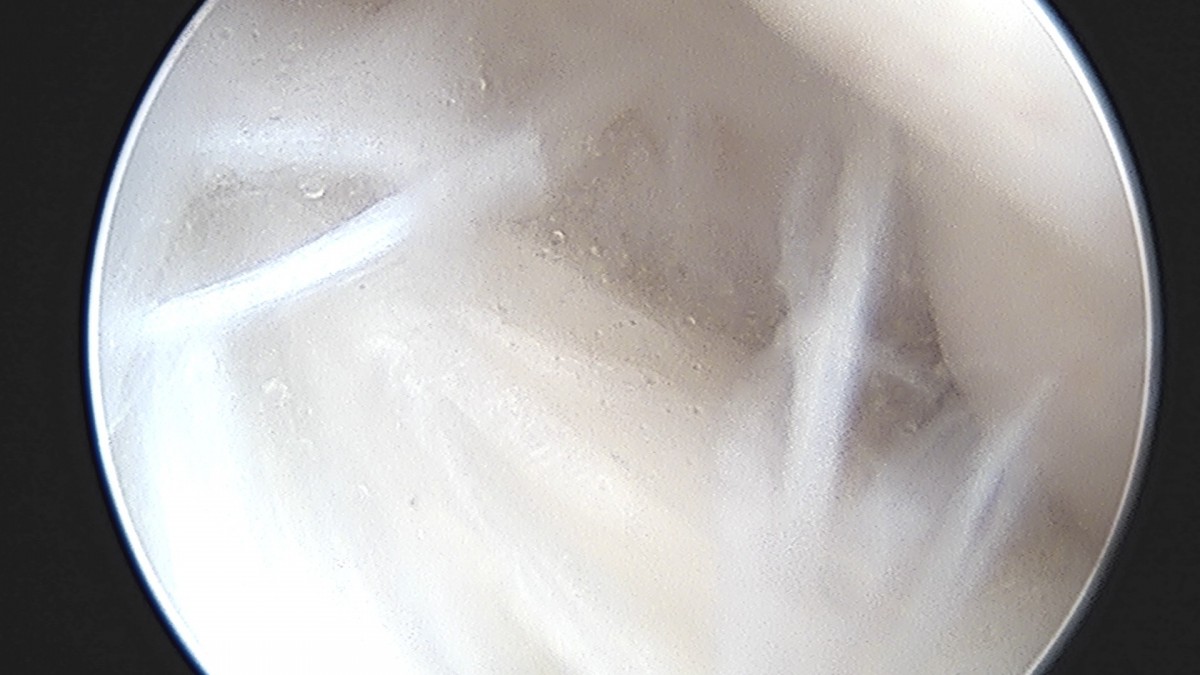

이재상원장님 무릎 반월상 연골판 절제술 박대O 환자

dae765e4d9ac96aee867c9d6292d8784_1758005045_2383.jpg